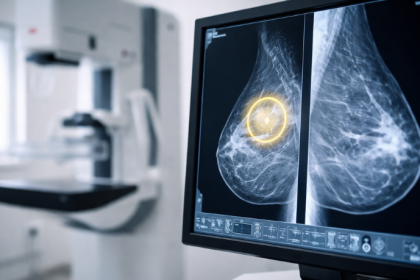

A mamografia pode detectar alterações antes dos sintomas? A análise de Vinicius Tadeu Sattin Rodrigues

A prevenção das doenças mamárias depende de diferentes estratégias de acompanhamento ao…